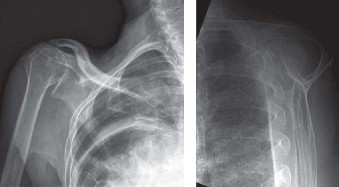

It should be noted that reverse total shoulder arthroplasty is also the procedure of choice in patients with cuff-tear arthropathy (aka rotator cuff arthropathy). Characteristics of cuff-tear arthropathy include superior migration of the humerus due to a massive rotator cuff tear, glenohumeral joint destruction, subchondral osteoporosis, and humeral head collapse (see Fig. 2–17). A reverse total shoulder

arthroplasty in this case serves the purpose of eliminating pain caused by glenohumeral joint arthritis while restoring functional motion and is the procedure of choice in patients with cuff-tear arthropathy.

Figure 2–17_X-rays of a patient showing evidence of cuff tear arthropathy. The humerus is migrated superiorly, the glenohumeral joint is destroyed, there is subchondral osteoporosis, and the humeral head is collapsed. (From Ecklund KJ, Lee TQ, Tibone J, Gupta R. Rotator cuff tear arthropathy. _J Am Acad Orthop Surg. 2007;15(6):340–349.)